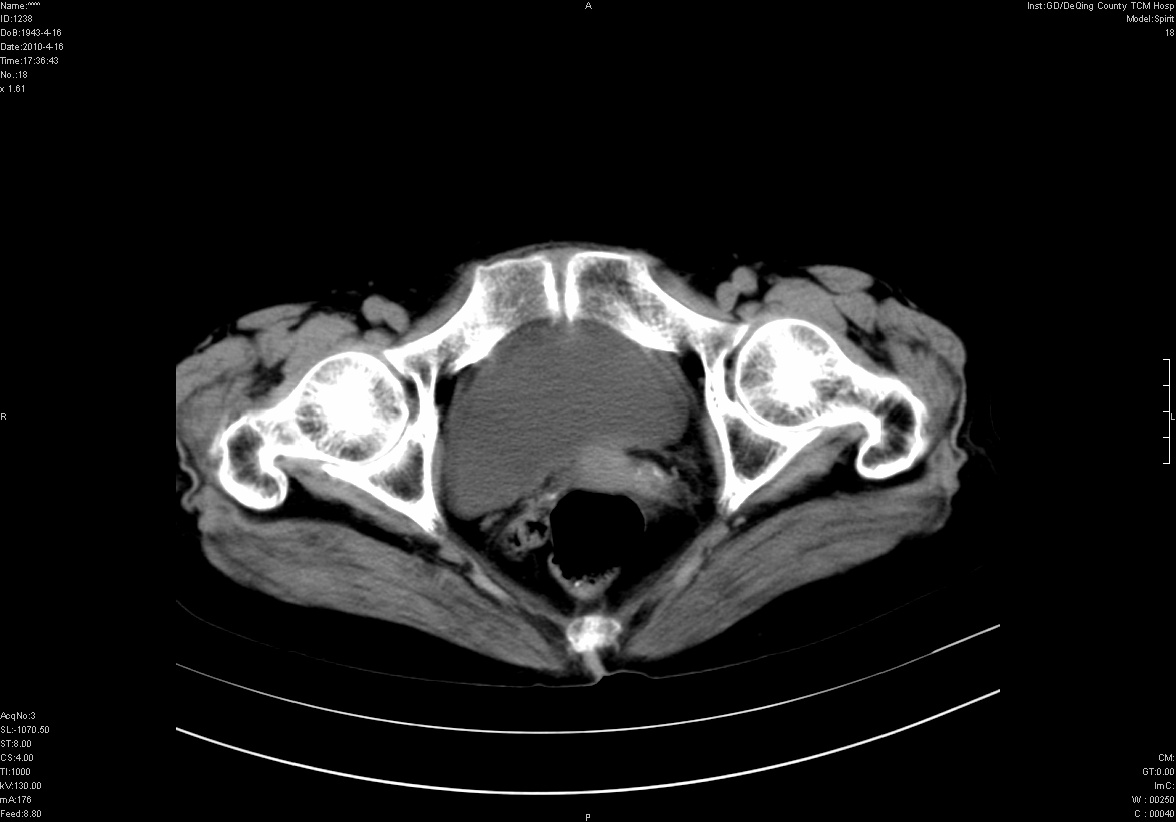

标题: CT25796:女,60岁,腹痛5天,请会诊??? [打印本页]

标题: CT25796:女,60岁,腹痛5天,请会诊???

考虑卵巢畸胎瘤。

支持右侧盆腔畸胎瘤。

右侧附件畸胎瘤

考虑右侧卵巢畸胎瘤。

考虑右侧卵巢畸胎瘤

右侧卵巢畸胎瘤可能。